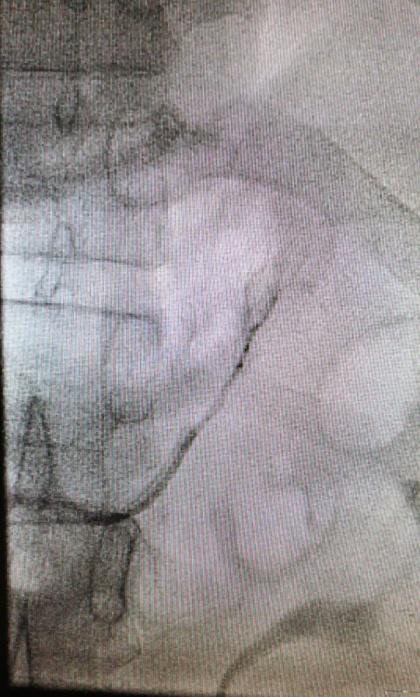

在征得患者及其家屬的同意后,我院多科協(xié)作行雙側(cè)腎上腺靜脈插管采血術(shù)。術(shù)中,僅僅在大腿根部局部皮膚麻醉,只需米粒大小一個針眼,通過股靜脈將導(dǎo)管通過很多道彎曲,分別送達(dá)左側(cè)和右側(cè)腎上腺靜脈。通過術(shù)中送檢血皮質(zhì)醇,證實雙側(cè)腎上腺靜脈插管成功。然后,手術(shù)醫(yī)生在雙側(cè)腎上腺靜脈和下腔靜脈同時取血。標(biāo)本送檢后,明確診斷為特發(fā)性醛固酮增多癥,左側(cè)腎上腺腺瘤無功能?;颊邿o需手術(shù),但需服用特殊的藥物控制血壓。在明確診斷后,心內(nèi)科立即為患者調(diào)整了降壓方案,針對特發(fā)性醛固酮增多癥進(jìn)行了針對性病因治療?;颊呒韧恢辈荒芸刂频难獕貉杆俚玫搅肆己每刂?。

右側(cè)腎上腺靜脈插管